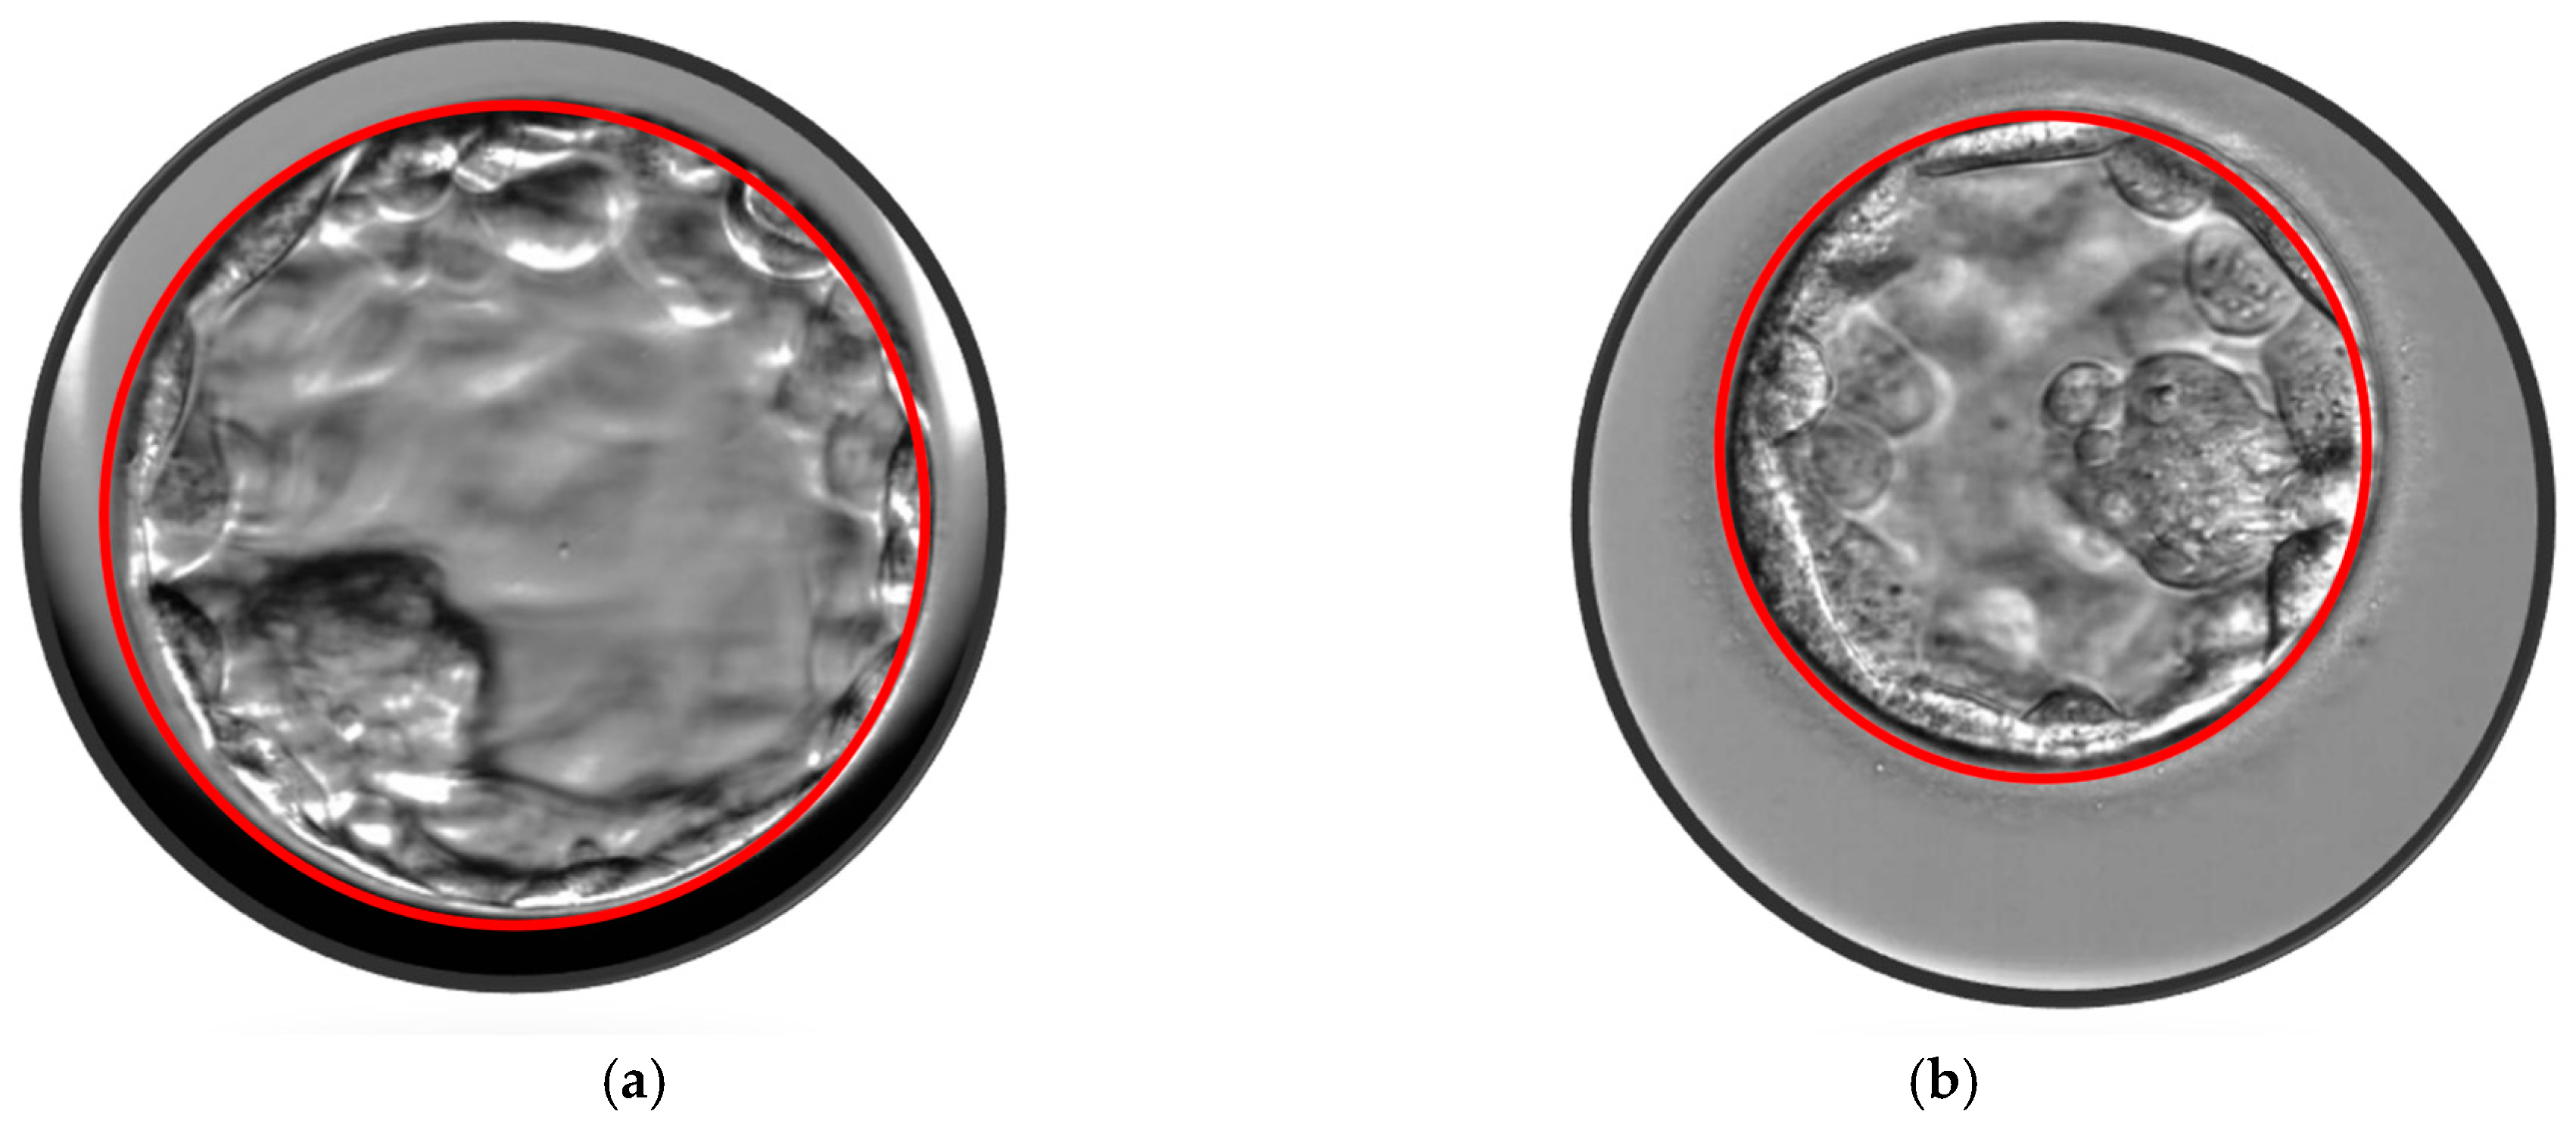

- Sciorio, R.; Thong, D.; Thong, K.J.; Pickering, S.J. Clinical pregnancy is significantly associated with the blastocyst width and area: A time-lapse study. J. Assist. Reprod. Genet. 2021, 38, 847–855. [Google Scholar] [CrossRef] [PubMed]

- Sciorio, R.; Meseguer, M. Focus on time-lapse analysis: Blastocyst collapse and morphometric assessment as new features of embryo viability. Reprod. Biomed. Online 2021, 43, 821–832. [Google Scholar] [CrossRef] [PubMed]

- Lagalla, C.; Barberi, M.; Orlando, G.; Sciajno, R.; Bonu, M.A.; Borini, A. A quantitative approach to blastocyst quality evaluation: Morphometric analysis and related IVF outcomes. J. Assist. Reprod. Genet. 2015, 32, 705–712. [Google Scholar] [CrossRef]

- Utsuno, H.; Ishimaru, T.; Matsumoto, M.; Sasamori, C.; Takahashi, H.; Kimura, H.; Kamijo, S.; Yamada, M.; Tanaka, M.; Hamatani, T. Morphometric assessment of blastocysts: Relationship with the ongoing pregnancy rate. F S Rep. 2022, 4, 85–92. [Google Scholar] [CrossRef] [PubMed]